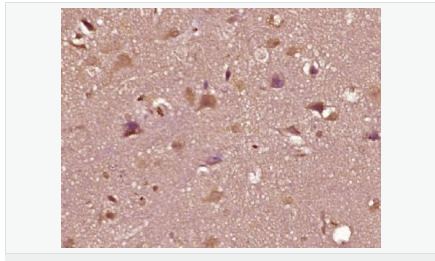

| 產(chǎn)品應(yīng)用 | WB=1:500-2000 ELISA=1:5000-10000 IHC-P=1:100-500 IHC-F=1:100-500 Flow-Cyt=1ug/Test IF=1:100-500 (石蠟切片需做抗原修復(fù)) not yet tested in other applications. optimal dilutions/concentrations should be determined by the end user. |

| 產(chǎn)品介紹 | The androgen receptor gene is more than 90 kb long and codes for a protein that has 3 major functional domains: the N-terminal domain, DNA-binding domain, and androgen-binding domain. The protein functions as a steroid-hormone activated transcription factor. Upon binding the hormone ligand, the receptor dissociates from accessory proteins, translocates into the nucleus, dimerizes, and then stimulates transcription of androgen responsive genes. This gene contains 2 polymorphic trinucleotide repeat segments that encode polyglutamine and polyglycine tracts in the N-terminal transactivation domain of its protein. Expansion of the polyglutamine tract causes spinal bulbar muscular atrophy (Kennedy disease). Mutations in this gene are also associated with complete androgen insensitivity (CAIS). Two alternatively spliced variants encoding distinct isoforms have been described. [provided by RefSeq, Jul 2008] Function: Steroid hormone receptors are ligand-activated transcription factors that regulate eukaryotic gene expression and affect cellular proliferation and differentiation in target tissues. Transcription factor activity is modulated by bound coactivator and corepressor proteins. Transcription activation is down-regulated by NR0B2. Activated, but not phosphorylated, by HIPK3 and ZIPK/DAPK3. [ENZYME REGULATION] AIM-100 (4-amino-5,6-biaryl-furo[2,3-d]pyrimidine) suppresses TNK2-mediated phosphorylation at Tyr-267. Inhibits the binding of the Tyr-267 phosphorylated form to androgen-responsive enhancers (AREs) and its transcriptional activity. Subunit: Binds DNA as a homodimer. Part of a ternary complex containing AR, EFCAB6/DJBP and PARK7. Interacts with HIPK3 and NR0B2 in the presence of androgen. The ligand binding domain interacts with KAT7/HBO1 in the presence of dihydrotestosterone. Interacts with EFCAB6/DJBP, PELP1, PQBP1, RANBP9, RBAK, SPDEF, SRA1, TGFB1I1, ZNF318 and RREB1. Interacts with ZMIZ1/ZIMP10 and ZMIZ2/ZMIP7 which both enhance its transactivation activity. Interacts with SLC30A9 and RAD54L2/ARIP4. Interacts via the ligand-binding domain with LXXLL and FXXLF motifs from NCOA1, NCOA2, NCOA3, NCOA4 and MAGEA11. The AR N-terminal poly-Gln region binds Ran resulting in enhancement of AR-mediated transactivation. Ran-binding decreases as the poly-Gln length increases. Interacts with HIP1 (via coiled coil domain). Interacts (via ligand-binding domain) with TRIM68. Interacts with TNK2. Interacts with USP26. Interacts with RNF6. Interacts (regulated by RNF6 probably through polyubiquitination) with RNF14; regulates AR transcriptional activity. Interacts with PRMT2 and TRIM24. Interacts with GNB2L1/RACK1. Interacts with RANBP10; this interaction enhances dihydrotestosterone-induced AR transcriptional activity. Interacts with PRPF6 in a hormone-independent way; this interaction enhances dihydrotestosterone-induced AR transcriptional activity. Interacts with STK4/MST1. Interacts with ZIPK/DAPK3. Interacts with LPXN. Interacts with MAK. Part of a complex containing AR, MAK and NCOA3. Subcellular Location: Nucleus. Cytoplasm. Note=Predominantly cytoplasmic in unligated form but translocates to the nucleus upon ligand-binding. Can also translocate to the nucleus in unligated form in the presence of GNB2L1. Tissue Specificity: Isoform 2 is mainly expressed in heart and skeletal muscle. Post-translational modifications: Sumoylated on Lys-386 (major) and Lys-520. Ubiquitinated. Deubiquitinated by USP26. 'Lys-6' and 'Lys-27'-linked polyubiquitination by RNF6 modulates AR transcriptional activity and specificity. Phosphorylated in prostate cancer cells in response to several growth factors including EGF. Phosphorylation is induced by c-Src kinase (CSK). Tyr-534 is one of the major phosphorylation sites and an increase in phosphorylation and Src kinase activity is associated with prostate cancer progression. Phosphorylation by TNK2 enhances the DNA-binding and transcriptional activity and may be responsible for androgen-independent progression of prostate cancer. Phosphorylation at Ser-81 by CDK9 regulates AR promoter selectivity and cell growth. Phosphorylation by PAK6 leads to AR-mediated transcription inhibition. Palmitoylated by ZDHHC7 and ZDHHC21. Palmitoylation is required for plasma membrane targeting and for rapid intracellular signaling via ERK and AKT kinases and cAMP generation. DISEASE: Defects in AR are the cause of androgen insensitivity syndrome (AIS) [MIM:300068]; previously known as testicular feminization syndrome (TFM). AIS is an X-linked recessive form of pseudohermaphroditism due end-organ resistance to androgen. Affected males have female external genitalia, female breast development, blind vagina, absent uterus and female adnexa, and abdominal or inguinal testes, despite a normal 46,XY karyotype. Defects in AR are the cause of spinal and bulbar muscular atrophy X-linked type 1 (SMAX1) [MIM:313200]; also known as Kennedy disease. SMAX1 is an X-linked recessive form of spinal muscular atrophy. Spinal muscular atrophy refers to a group of neuromuscular disorders characterized by degeneration of the anterior horn cells of the spinal cord, leading to symmetrical muscle weakness and atrophy. SMAX1 occurs only in men. Age at onset is usually in the third to fifth decade of life, but earlier involvement has been reported. It is characterized by slowly progressive limb and bulbar muscle weakness with fasciculations, muscle atrophy, and gynecomastia. The disorder is clinically similar to classic forms of autosomal spinal muscular atrophy. Note=Caused by trinucleotide CAG repeat expansion. In SMAX1 patients the number of Gln ranges from 38 to 62. Longer expansions result in earlier onset and more severe clinical manifestations of the disease. Note=Defects in AR may play a role in metastatic prostate cancer. The mutated receptor stimulates prostate growth and metastases development despite of androgen ablation. This treatment can reduce primary and metastatic lesions probably by inducing apoptosis of tumor cells when they express the wild-type receptor. Defects in AR are the cause of androgen insensitivity syndrome partial (PAIS) [MIM:312300]; also known as Reifenstein syndrome. PAIS is characterized by hypospadias, hypogonadism, gynecomastia, genital ambiguity, normal XY karyotype, and a pedigree pattern consistent with X-linked recessive inheritance. Some patients present azoospermia or severe oligospermia without other clinical manifestations. Similarity: Belongs to the nuclear hormone receptor family. NR3 subfamily. Contains 1 nuclear receptor DNA-binding domain. SWISS: P10275 Gene ID: 367 Database links: Entrez Gene: 367 Human Entrez Gene: 11835 Mouse Omim: 313700 Human SwissProt: P10275 Human SwissProt: P19091 Mouse Unigene: 496240 Human Unigene: 39005 Mouse Unigene: 394224 Mouse Unigene: 439657 Mouse Unigene: 9813 Rat Important Note: This product as supplied is intended for research use only, not for use in human, therapeutic or diagnostic applications. AR是一個(gè)由917個(gè)氨基酸組成的蛋白質(zhì),位于雄激素靶組織細(xì)胞中或細(xì)胞表面上的特異分子部位或結(jié)構(gòu)。 AR在前列腺癌中起著重要的作用,研究表明AR的表達(dá)與組織分型形成一定的相關(guān)性 ,AR在高分化的腫瘤中表達(dá)較多,而在低分化的腫瘤中表達(dá)較少。用于前列腺癌的檢測(cè),指導(dǎo)臨床治療,目前可用于乳腺癌、食道癌等各項(xiàng)腫瘤的研究。 |